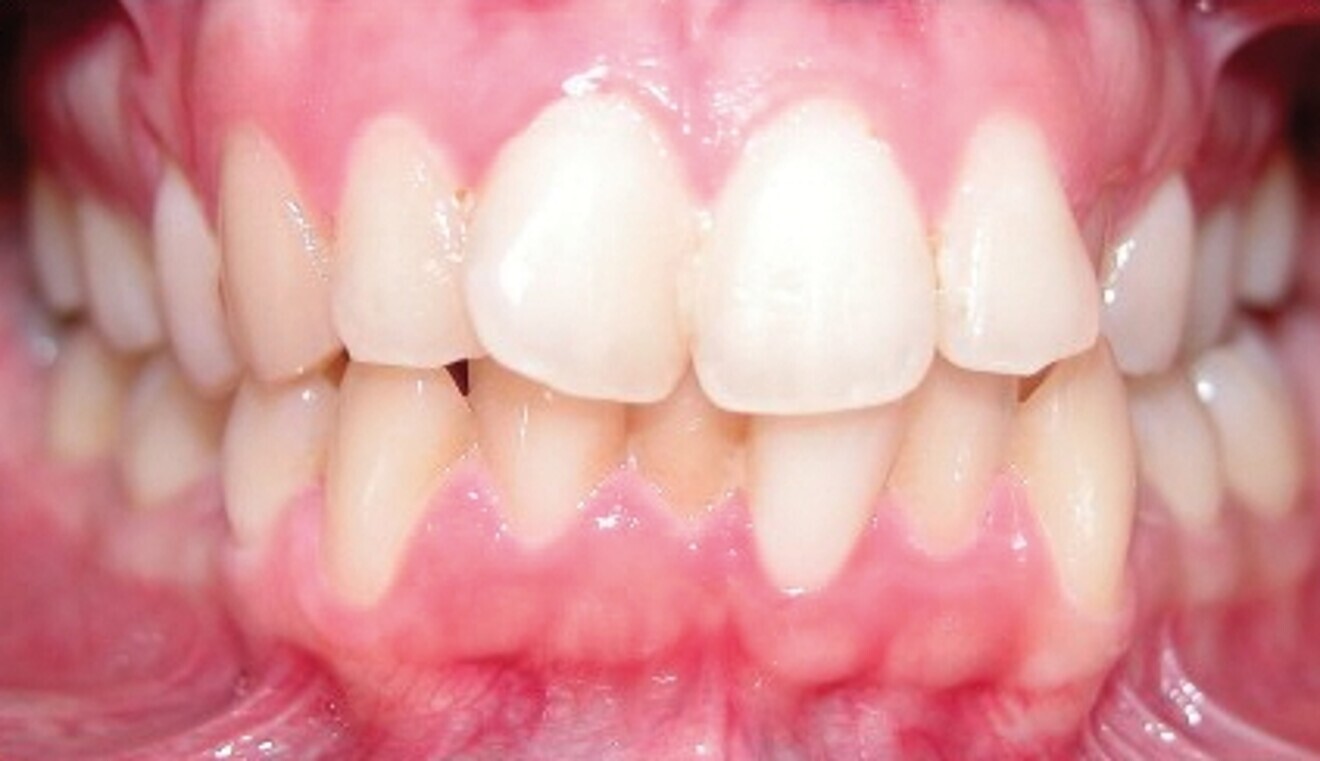

Le motif principal de consultation de la patiente, une jeune femme de 27 ans, est un encombrement dentaire accompagné d’une occlusion mal équilibrée. Danseuse de profession, elle se tracasse énormément au sujet de son apparence lors de ses apparitions publiques si elle entreprend un traitement. L’examen clinique révèle une relation d’Angle de classe I du côté droit et une relation molaire canine de classe II du côté gauche (Fig. 1).

De ce côté, les molaires, les prémolaires et la canine sont en occlusion croisée. L’examen ne montre aucun déplacement latéral fonctionnel de la mandibule. La ligne médiane maxillaire est en harmonie avec la symétrie faciale, mais la ligne médiane mandibulaire est déviée vers la gauche, en raison d’un décalage des dents de 4 mm. On observe un encombrement important des dents inférieures, évalué à 11 mm, et un encombrement modéré de 10 mm au niveau de l’arcade maxillaire. Les racines des dents 31, 33 et 43 semblent proches du rebord vestibulaire de l’os cortical, et les deux arcades présentent un rétrécissement dans la région des prémolaires et molaires.

Fig. 1d : Photographie intraorale initiale.